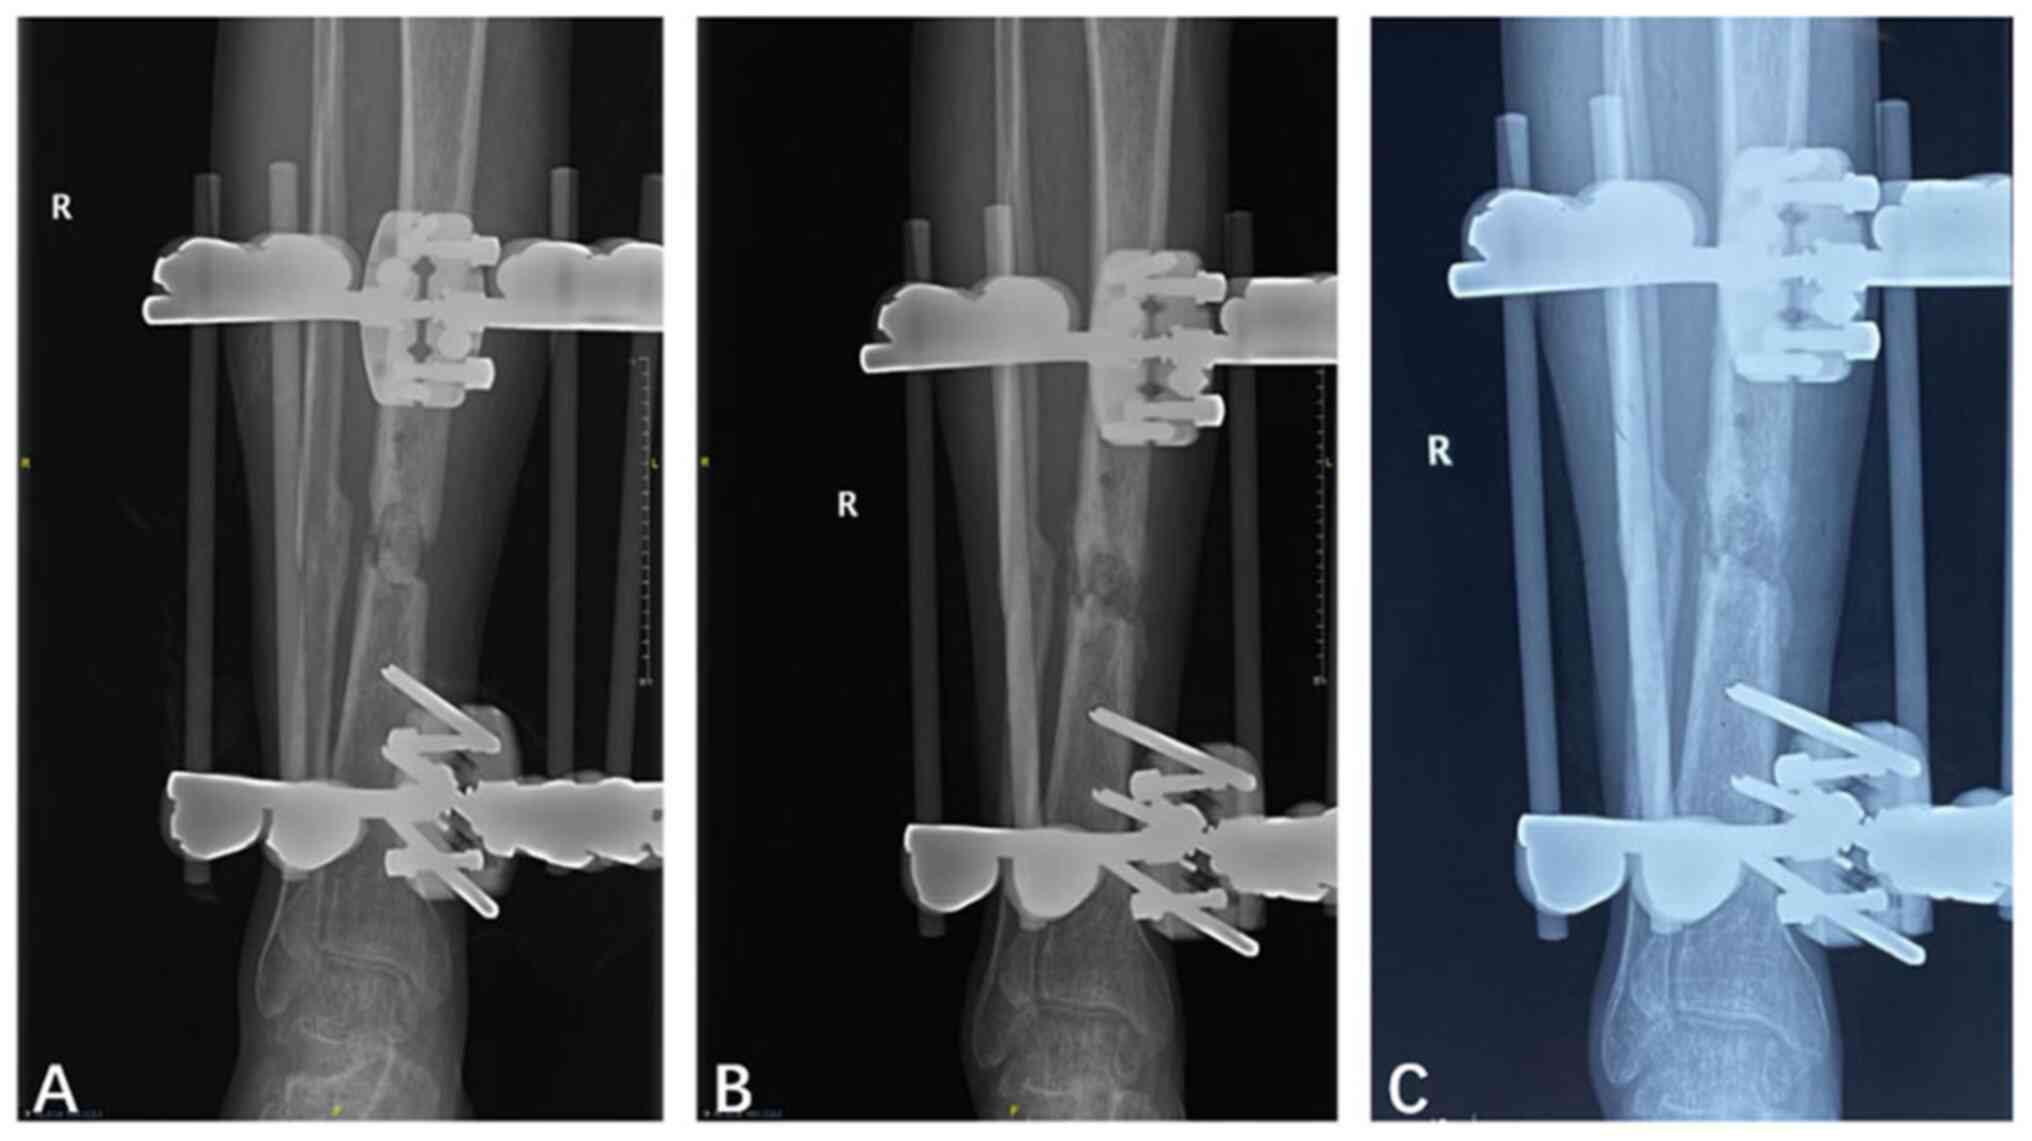

In the IX group, 12 patients achieved bone union (92.3%), with a median union time of 13.1 months (Table I), while 1 patient had bone non-union. Only 2 patients (15.4%) in this group had infection recurrence. In addition, 1 patient had 9˚ malrotation of the affected limb but did not undergo further surgery and 3 patients had postoperative leg shortening (1.0-2.3 cm), while no patients had a tibial varus of >2˚. The proportion of patients in the IX group with a satisfactory functional status following surgery was 92.3%, which was significantly higher than that in the EX group (P=0.034; Table III). Representative follow-up X-ray images of patients who underwent bone grafting and changed to internal fixation are shown in Fig. 2.

Figure 2

Representative X-rays of a patient (no. 26) who underwent bone grafting and changed to an internal fixator. (A) Cement spacer placed in the bone defect via unilateral external fixation to maintain tibial stability prior to second-stage surgery. (B) Bone defect filled with autogenous iliac bone grafts and callus formation 3 months after the second-stage surgery during which the external fixator was changed to an internal fixator. (C) Recovered continuity of the cortical bone 1 year after the second-stage surgery. R, right.